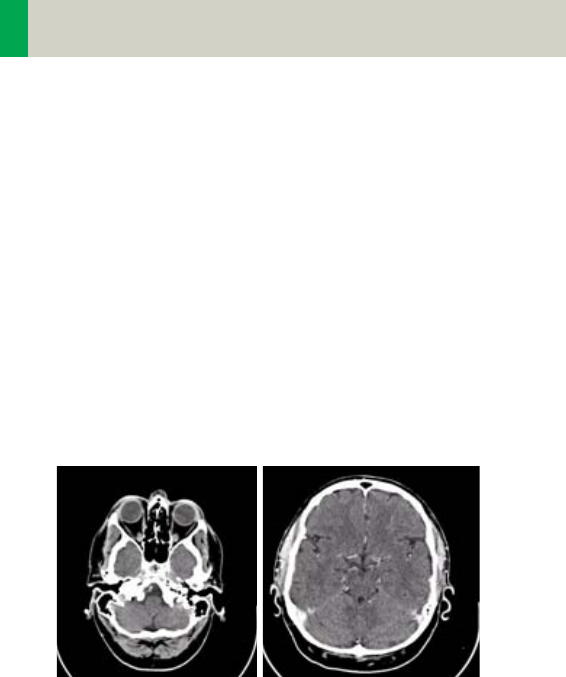

Automatic Bone Correction

The head protocols provide significant improvements

regarding image quality for heads. An automatic bone

correction algorithm has been included in the standard

image reconstruction. Using a new iterative technique,

typical artifacts arising from the beam-hardening

effect, for example, Hounsfield bar, are minimized

without additional post-processing. This advanced

algorithm produces excellent images of the posterior

fossa, but also improves head image quality in general.

Bone correction is activated automatically for body

region “Head”. The reconstruction algorithm for “Head”

also employs special adaptive convolution kernels

which help to improve the sharpness-to-noise ratio.

More precisely, anatomic contours are clearly dis-

played while noise is suppressed at the same time

without causing a blurring of edges.

Head image without

correction.

Head image with

corrections.